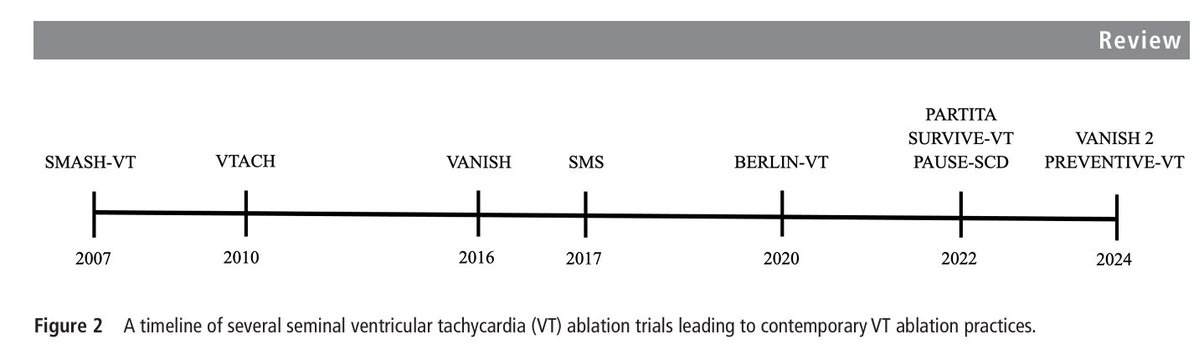

⚡️Ventricular tachycardia ablation in ischaemic cardiomyopathy: who, when & how? @Heart_BMJ #Cardiology #CardioEd #CardioX